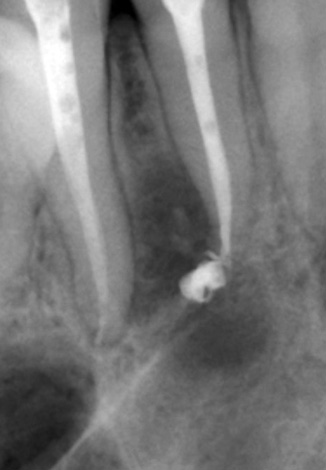

A fotografia abaixo mostra um dente com um cisto na raiz:

É impossível deixar esse foco de infecção sem tratamento, ou seja, neste caso, o problema é crítico para o destino posterior do dente. Um canal dentário não tratado deixado intocado, mais cedo ou mais tarde, forçará o paciente a consultar um médico novamente, e às vezes a única opção é remover o dente em meio à exacerbação da periodontite.